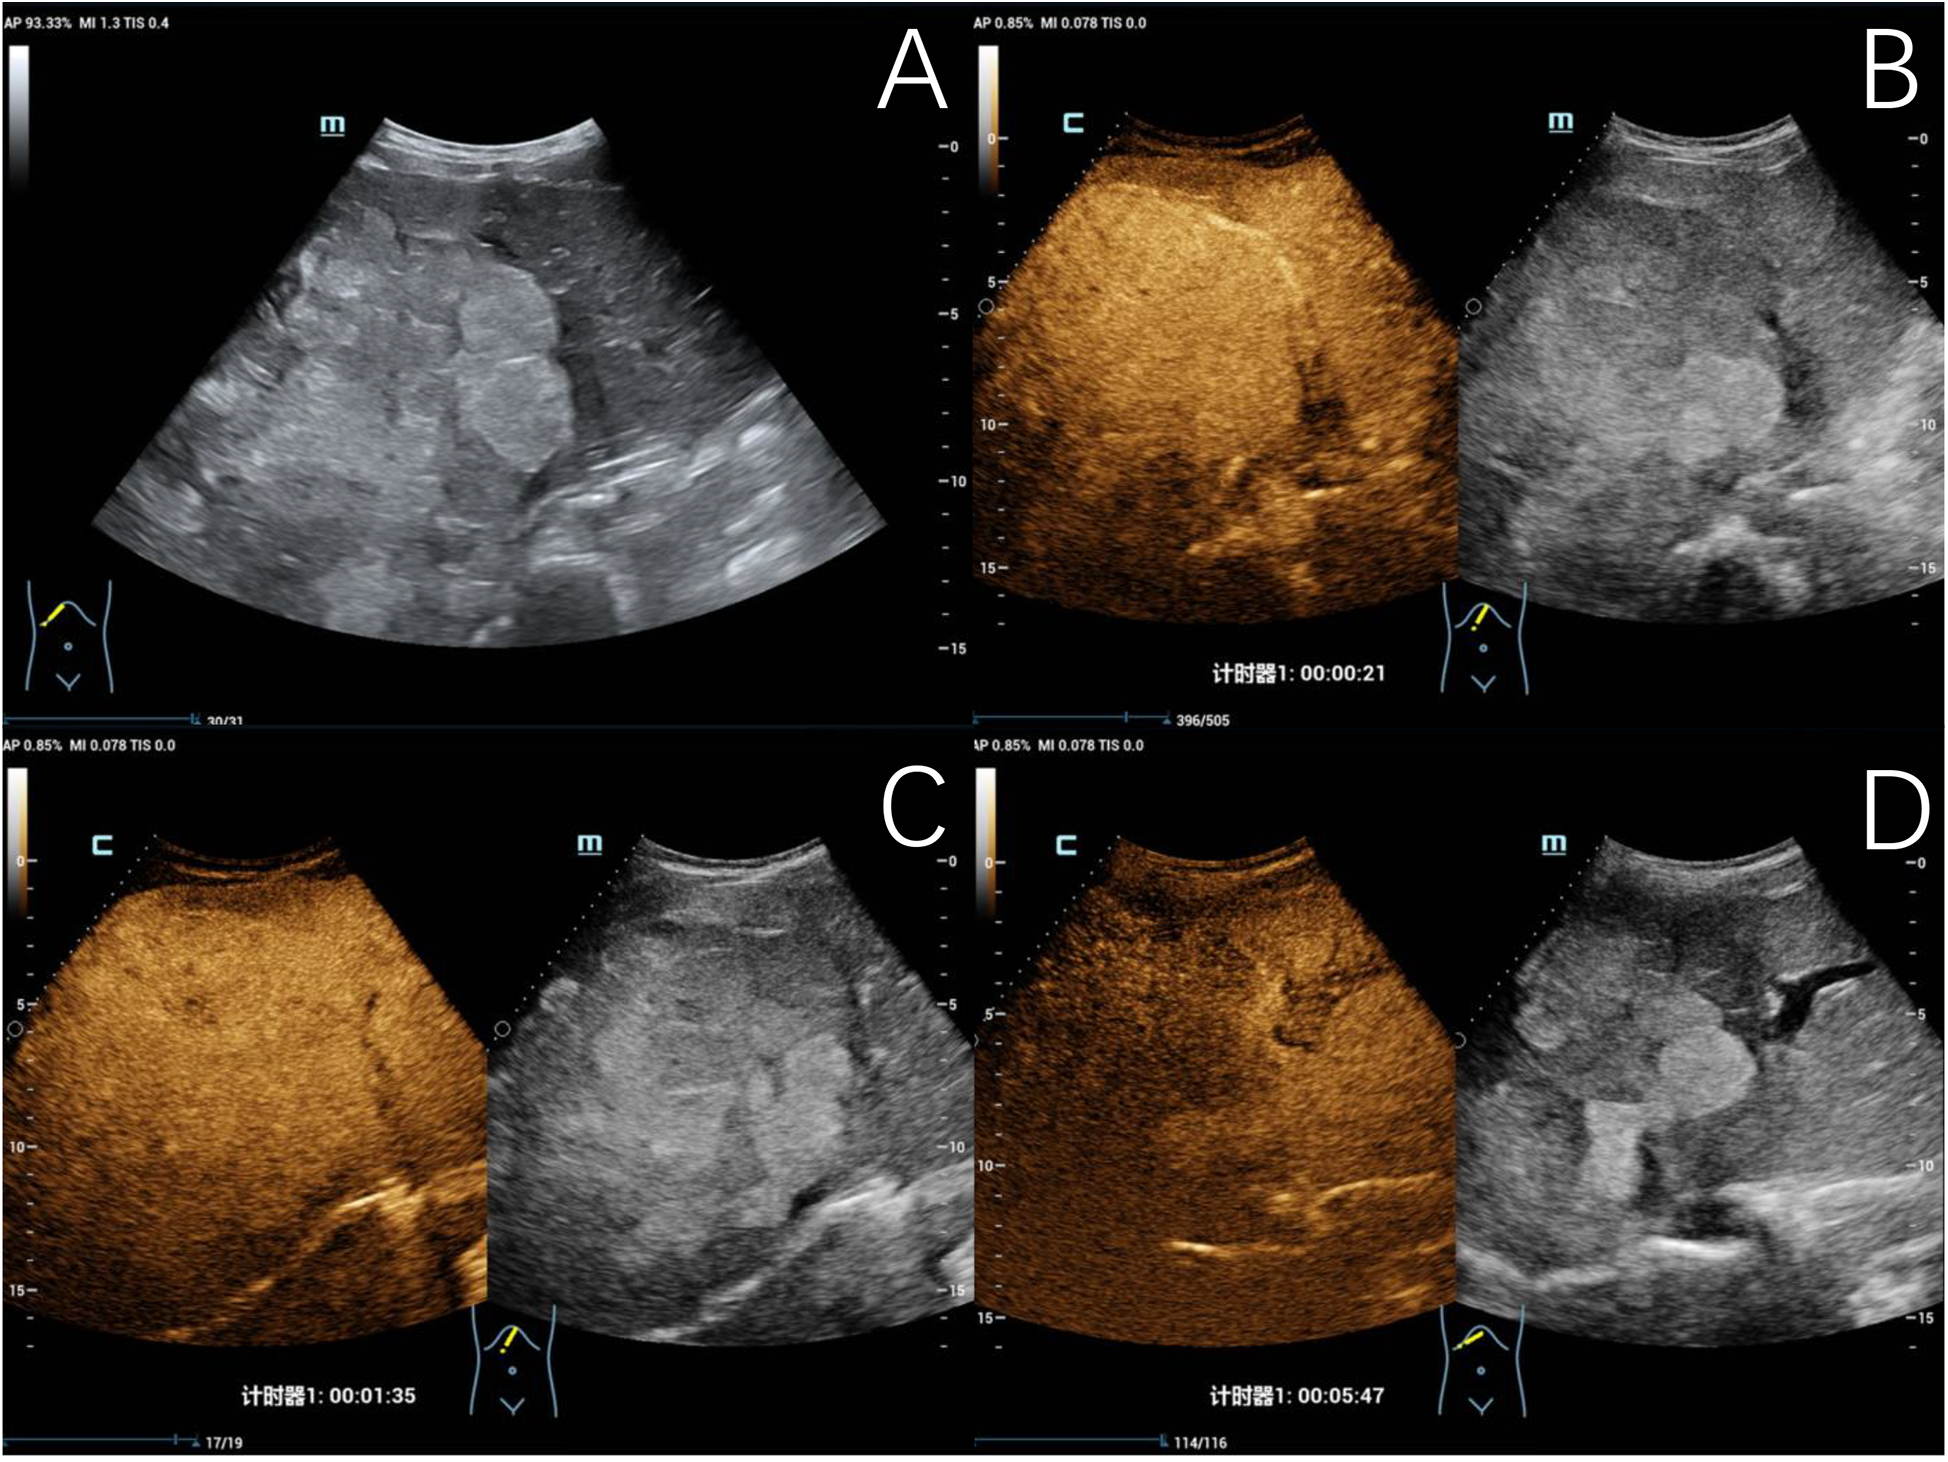

Two out of 31 children of hepatic echinococcosis underwent CEUS. Nine out of 36 children with hepatoblastoma underwent CEUS. One hepatic CE lesion showed no significant enhancement during the arterial, portal venous, and late phases (Figure 2). One hepatic AE lesion showed slight peripheral enhancement during the arterial phase (Figure 3). Nine hepatoblastoma lesions showed hyperenhancement during the arterial phase, six lesions began to washout in the portal venous phase, and nine lesions showed hypoenhancement in the late phase (Figure 4).

Figure 4

www.frontiersin.org

Figure 4. Typical ultrasound findings of hepatoblastoma (case 3). Ultrasound revealed a mixed echogenic mass in the right liver and left inner lobe, with clear boundaries, irregular morphology, and a maximum diameter of 140 mm (A) contrast-enhanced ultrasound examination showed heterogeneous hyperenhancement in the arterial phase (B), isoenhancement in the portal venous phase (C), and hypoenhancement in the late phase (D), with patchy non-enhancing areas observed within.